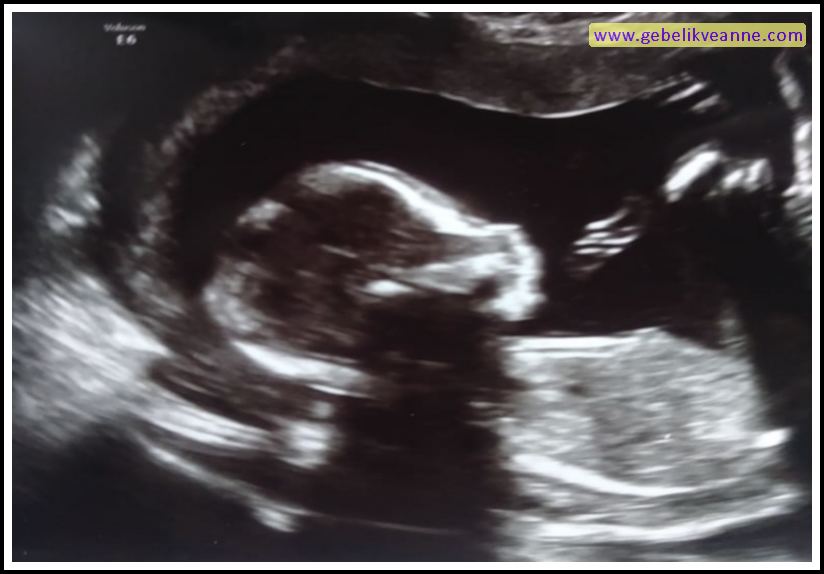

13 Haftalık Gebelik Ultrason Görüntüsü

Source: www.gebelikveanne.com

13 haftalık bebek görüntüsü 4 boyutlu Ovula erken gebelik testi yorum ovula erken gebelik testi yorum13 haftalık hamilelikte 4. 34 haftalik bebek ultrason görüntüsü üç veya dört boyutlu ultrason gebeliğin ilk aylarından itibaren yapılabilmektedir. 8 haftalık hareket eden fetus görüntüsü. Haftası video anlatım için tıklayın gebeliğin 13. Gebelik haftasında bebeğin boyu yaklaşık olarak 7 cm, ağırlığı 25 gram kadardır. Artık bebeğinizin başı vücudunun yarısı kadar değil, yani vücudu. 13 haftalık hamilelik ultrason görüntüsü. 12 haftalık gebelik cinsiyet görüntüsü.

13 haftalık bebekte derinin üzeri ince tüylerle kaplanmıştır. 13 haftalık gebelik ultrason görüntüleri videosu. Hamilelikte (gebelikte) bebeğin cinsiyeti ultrason ile çok yüksek oranda tespit edilebilmektedir. 2 ve 3 boyutlu ultrason görüntüsü. 13 haftalık hamilelikte ultrason muayenesi sırasında bebek önceki haftalara oranla çok daha net bir şekilde görülebilir. Haftadan itibaren bebek artık etrafının farkına varmaya başlar.rahmin içi zifiri karanlık gibi düşünülse de anne adayının bulunduğu çevreye bağlı olarak aydınlık yada karanlık olabilir. Gebelikte 23 hafta 3d ve 4 boyutlu ultrason görüntüsü. 20 haftalık bebeğin 4 boyutlu ultrasın görüntüsü. Kullandığımız cihaz 3d/4d özelliği olan gelişmiş bir cihazdır.

15 haftalık bebeğin 4 boyutlu ultrason görüntüsü. Haftada bebeğinizin tüm organları ve vücut sistemleri oluşmuştur. 12 haftalık gebelik döneminin bir güzel yanı da bu hafta bebeğin cinsiyetine dair bir ipucu edine bilirsiniz! 13 haftalık gebelik görüntüsü birçok anne tarafından merak edilmektedir. Güner uysal ameliyatsız burun estetiği. 13 haftalık hamilelikte ultrason muayenesi sırasında bebek önceki haftalara oranla çok daha net bir şekilde görülebilir.

Bu sayede gebeliğin erken dönemlerinde cinsiyet, yarık damak, yarık. Haftadan itibaren bebek artık etrafının farkına varmaya başlar.rahmin içi zifiri karanlık gibi düşünülse de anne adayının bulunduğu çevreye bağlı olarak aydınlık yada karanlık olabilir. 13 haftalık hamilelikte ultrason muayenesi sırasında bebek önceki haftalara oranla çok daha net bir şekilde görülebilir.